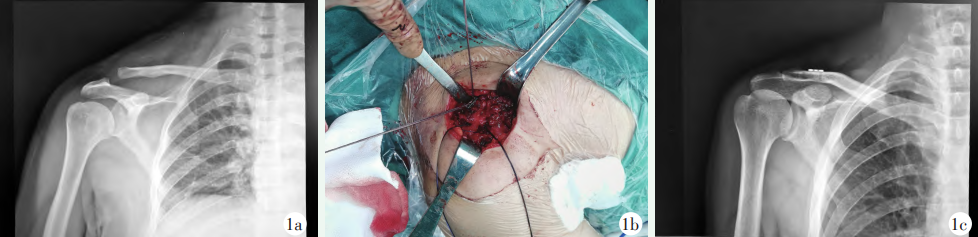

После успешной общей анестезии пациентку уложили на спину. Сделайте продольный разрез длиной около 4 см от клювовидного отростка до акромиально-ключичного сустава, чтобы обнажить акромиально-ключичный сустав, дистальный конец ключицы и основание клювовидного отростка. Сделайте разрез на расстоянии около 3 см от акромиально-ключичного сустава посередине и спереди. 1/3 ключицы и сделайте разрез в медиальном и латеральном направлениях соответственно. Используйте спицу Киршнера диаметром 2,5 мм, чтобы создать костный канал на ключице длиной 0,5 см, и наложите рассасывающийся шов № 1 в качестве резервной линии вытяжения. Разберите фиксирующий трос стальной пластины петли и тяговый трос для дальнейшего использования. Тракционная спица петлевой пластинки обходит основание клювовидного отростка, а двухниточная фиксирующая спица выводится из медиального костного канала ключицы, основания клювовидного отростка и латерального костного канала ключицы последовательно с помощью техника прохождения проволоки. Два конца фиксирующей проволоки пропускают через отверстия стальной пластины в форме полоски и сокращают акромиально-ключичный сустав.Используя узел Ниццы, постепенно затягивайте его до тех пор, пока акромиально-ключичный сустав не станет слегка чрезмерно уменьшенным, а затем завяжите и завяжите. исправьте это (рис. 1б). Просверлите отверстия на передне-латеральной стороне дистальной части ключицы, наложите рассасывающиеся швы № 1 и зашейте акромиально-ключичную связку и капсулу сустава позади акромиона в виде цифры «8», промойте разрез и зашейте слой за слоем. Послеоперационная рентгенография показала соответствующее чрезмерное сокращение акромиально-ключицы (рис. 1в).

Рисунок 1. Пациент, мужчина, 46 лет. 1а: Рентгенограмма плечевого сустава в передне-задней проекции: вывих правого акромиально-ключичного сустава III типа по Роквуду; 1б: Во время операции линия фиксации проходит через лоскут, а рассасывающиеся части оставляются для восстановления клювовидно-ключичной связки, акромиально-ключичной связки и Суставная капсула соответственно.Линия 1c: Послеоперационная переднезадняя рентгенограмма показывает соответствующее чрезмерное сокращение акромиально-ключичного сустава.